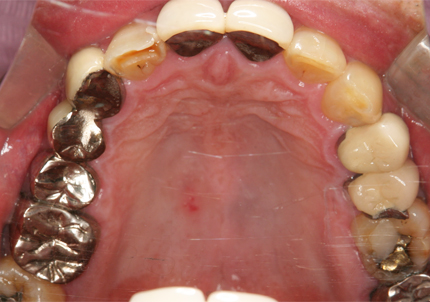

患者:S.G様(55歳/男性)

初診日 :2014年6月10日

主訴 :義歯が嫌いで使わず奥歯が咬めないので、全体の治療を希望する

1.初診時口腔内写真(2014年6月)